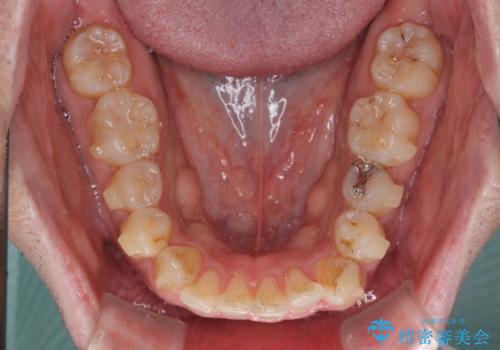

破折して抜歯が必要となった歯の後ろの歯は、根管治療が必要な状態であったので、根管治療を行い、矯正治療後にインプラント部の補綴治療と同時にセラミッククラウンを装着しました。

矯正治療以外に費用負担がかかることになりましたが、気になるところ全てを処置することができ、患者様には大変満足していただきました。